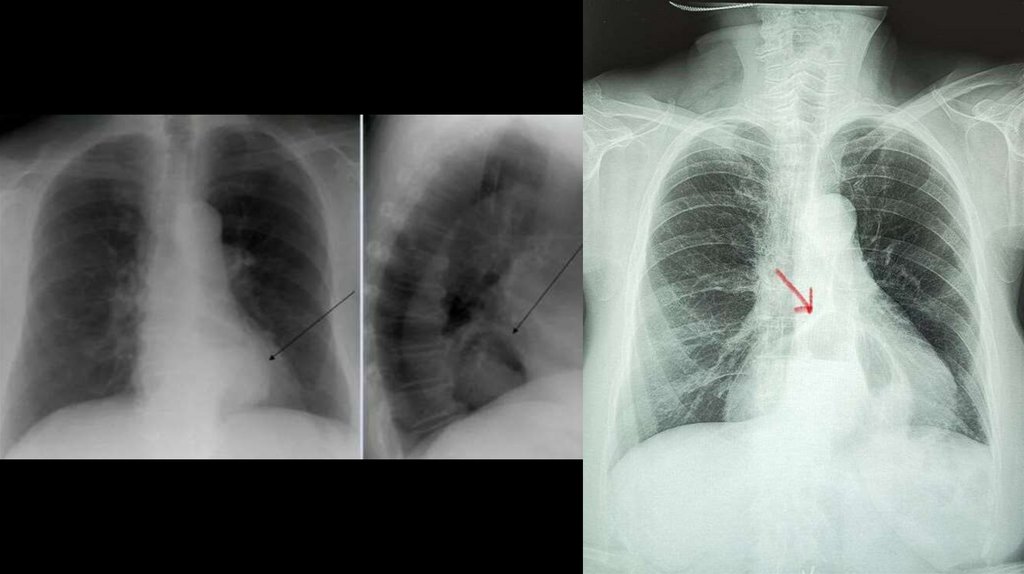

• (Слева) На рентгенограмме пищевода, выполненной во время рентгеноскопии у женщины 29 лет с дисфагией и одышкой, визуализируется

расширенный, атоничный пищевод со стриктурой в дистальных отделах. Перистальтика пищевода полностью отсутствует. (Справа) На КТ

органов грудной клетки у этой же пациентки определяется интерстициальный фиброз, а также визуализируется в значительной степени

расширенный пищевод; оба обнаруженных изменения являются следствием склеродермии.